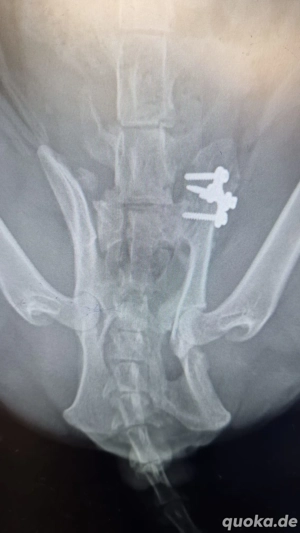

Vor etwa 3 Monaten wurde Batman leider von einem Auto angefahren. Zum Glück hat ihn eine liebe Dame gefunden, die ihm sofort zum Tierarzt brachte. Batman musste zweimal operiert werden. Anfang Dezember wurde die Platte entfernt. Die Fixierung mit Schrauben gehörte zur ersten OP.